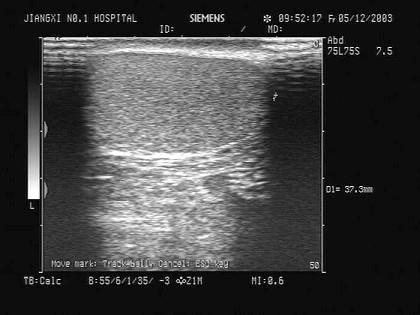

问题 该图为睾丸声像图,最可能的诊断为?(?)

选项 A.正常回声 B.急性睾丸炎 C.睾丸扭转 D.慢性睾丸炎 E.睾丸肿瘤

答案 A